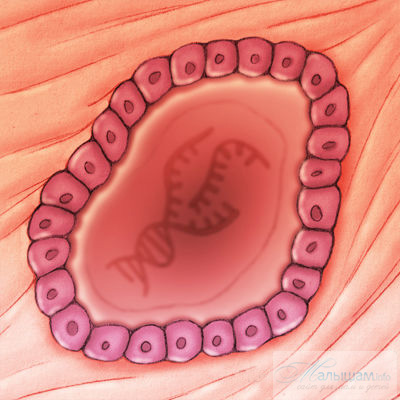

Таким чином, загальне погіршення самопочуття цілком може свідчити про доконаний зачатті. Така зміна стану жінки викликано тим, що запліднена яйцеклітина містить в собі чужорідні речовини, а організм при цьому починає реагувати на неї, як на хвороботворний вірус, тобто підвищенням температури намагається збільшити вироблення антитіл. На щастя, в цей же час в жіночому організмі декілька знижується рівень імунітету, тому до крайнощів (тобто до знищення заплідненого ембріона) справа доходить вкрай рідко.

підвищення базальної температури при овуляції свідчить у складних біохімічних процесах в організмі, і механізм дії гормнона прогестерону